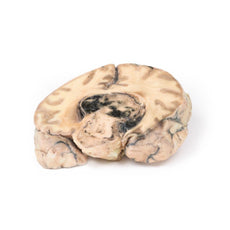

3D Printed Metastatic Carcinoma in the Brain

Pathology

The specimen is the cerebrum sliced horizontally. On the superior view, the right hemisphere is

clearly enlarged, particularly in the parietal region where the gyrae are widened and 3 cystic tumours are

evident. The largest, 5 cm in diameter, is in the right parietal region. A smaller tumour, 2 x 1.5 cm in

diameter, is seen close to the posterior margin of the largest tumour. A third one, 1.5 cm in diameter, is

present in the left parietal region. The tumours have mainly involved white matter. The wall of each lesion is

composed of shaggy friable greyish tissue. At necropsy, there was ulceration of the largest tumour into the

right lateral ventricle (seen more clearly when the inferior surface is examined). Sub-falcine herniation was

also seen, as is displacement of the basal ganglia and internal capsule. Histological examination revealed

metastatic carcinoma in the viable areas. Other metastases were found in the liver and bone. Histology of a

liver metastasis was consistent with origin from a primary carcinoma of breast.